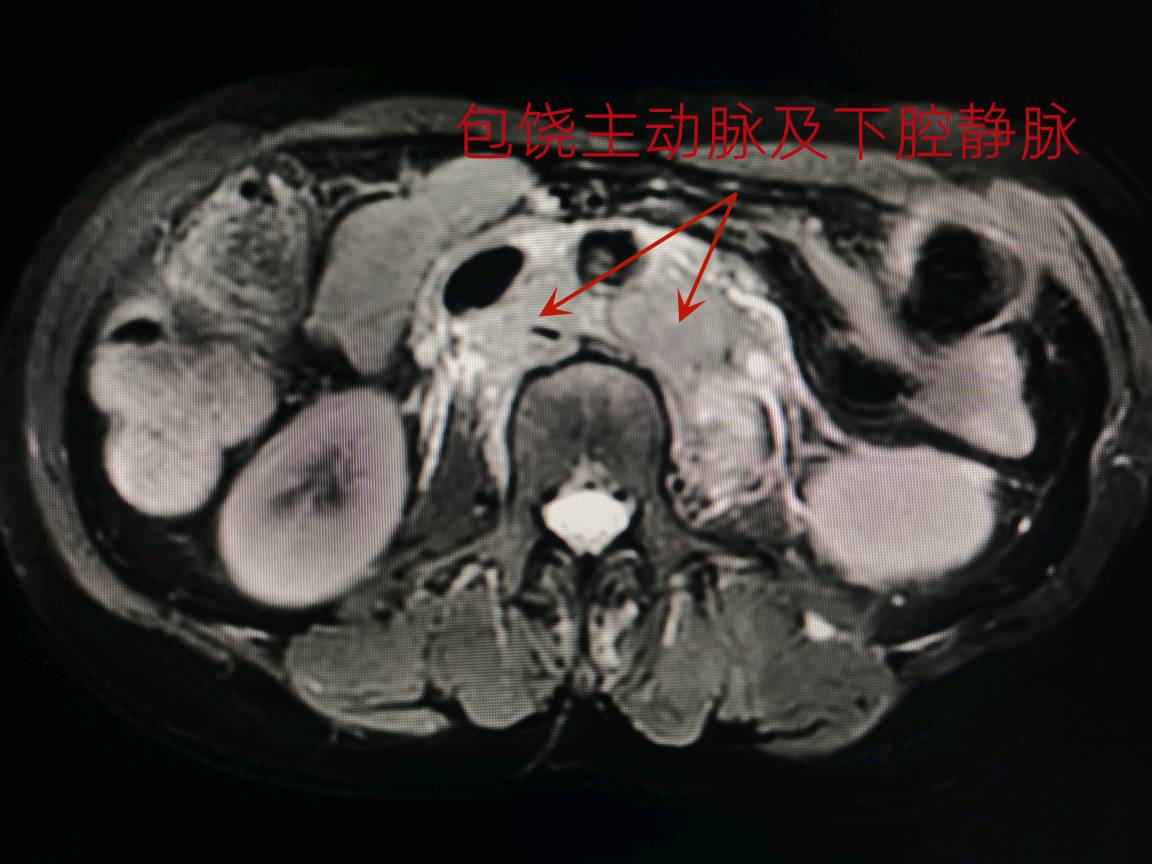

柯女士是一位45岁的中年女性,有着姣好的面容、高挑的身材和开朗的性格。2022年5月,她突然感到左侧腰背部持续疼痛,无法进食,经过一系列检查后被诊断为左侧肾盂癌伴腹膜后巨大淋巴结转移,侵及周围肌肉和腰椎,侵及左肾动脉并包绕大部分主动脉。这样在左侧腹部形成一个直径近10cm,长度超过15cm的与血管、腰肌、椎体相融合的固定不动的巨大肿瘤。

经过充分的术前准备,我们于2022年6月14日为患者进行了手术治疗,术中切除了左侧肾脏、肾上腺、主动脉周围淋巴结、肿瘤侵犯的肌肉和部分腰椎横突;肿瘤侵及的部分主动脉,也进行了部分切除和修补(注:主动脉是人体最大动脉,一般只有心脏和大血管外科医生能进行修补),并在腰椎侵犯处放钛夹标注将来放疗部位。